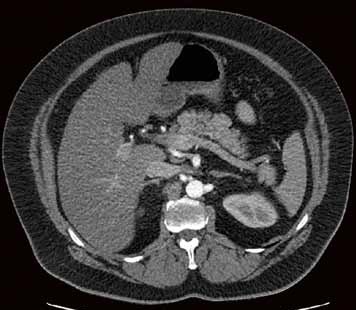

Die Klinik verfügt über 14 Computertomographen (CT), zwölf Magnetresonanztomographen (MRT) sowie zahlreiche Ultraschallgeräte. Allein am Campus Benjamin Franklin führen die Radiologen an sieben Tagen die Woche je zwischen 50 und 60 CT Untersuchungen täglich durch. Seit knapp drei Monaten steht ihnen dazu der neue 160-Schicht-Low-Dose-CT Aquilion PRIME zur Verfügung. Ein weiterer Aquilion PRIME sowie ein 640-Schicht-Volumen-CT Aquilion ONE ViSION EDITION wurden am Campus Mitte installiert. „Als wir nach einem neuen CT gesucht haben, war klar, dass dessen Ausstattung allen universitären diagnostischen Anforderungen gerecht werden muss", erklärt Dr. Stefan Niehues, Radiologe und Oberarzt der Klinik für Radiologie am Campus Benjamin Franklin.

„Mit dem neuen CT Aquilion PRIME können wir das komplette radiologische Spektrum der Charité abdecken. „Die gesamte Polytrauma-Diagnostik über die Akutversorgung bis hin zur Neuroradiologie und Diagnostik bei jungen Menschen führen wir mit dem Aquilion PRIME durch."

Neben der Rechnergeschwindigkeit lautet das Schlüsselwort bei dem neuen Gerät „Adaptive Iterative Dosis-Reduktion (AIDR 3D)". „Dieser mathematische Algorithmus erlaubt es uns, mit einem Bruchteil der Dosis zu arbeiten, die wir bisher für die erforderliche Bildqualität benötigt haben", weiß der Radiologe.

„Durch die Spitzentechnologie können wir bei gleich hoher Bildqualität die Dosis an Röntgenstrahlung bei vielen Untersuchungen auf ein Drittel reduzieren."